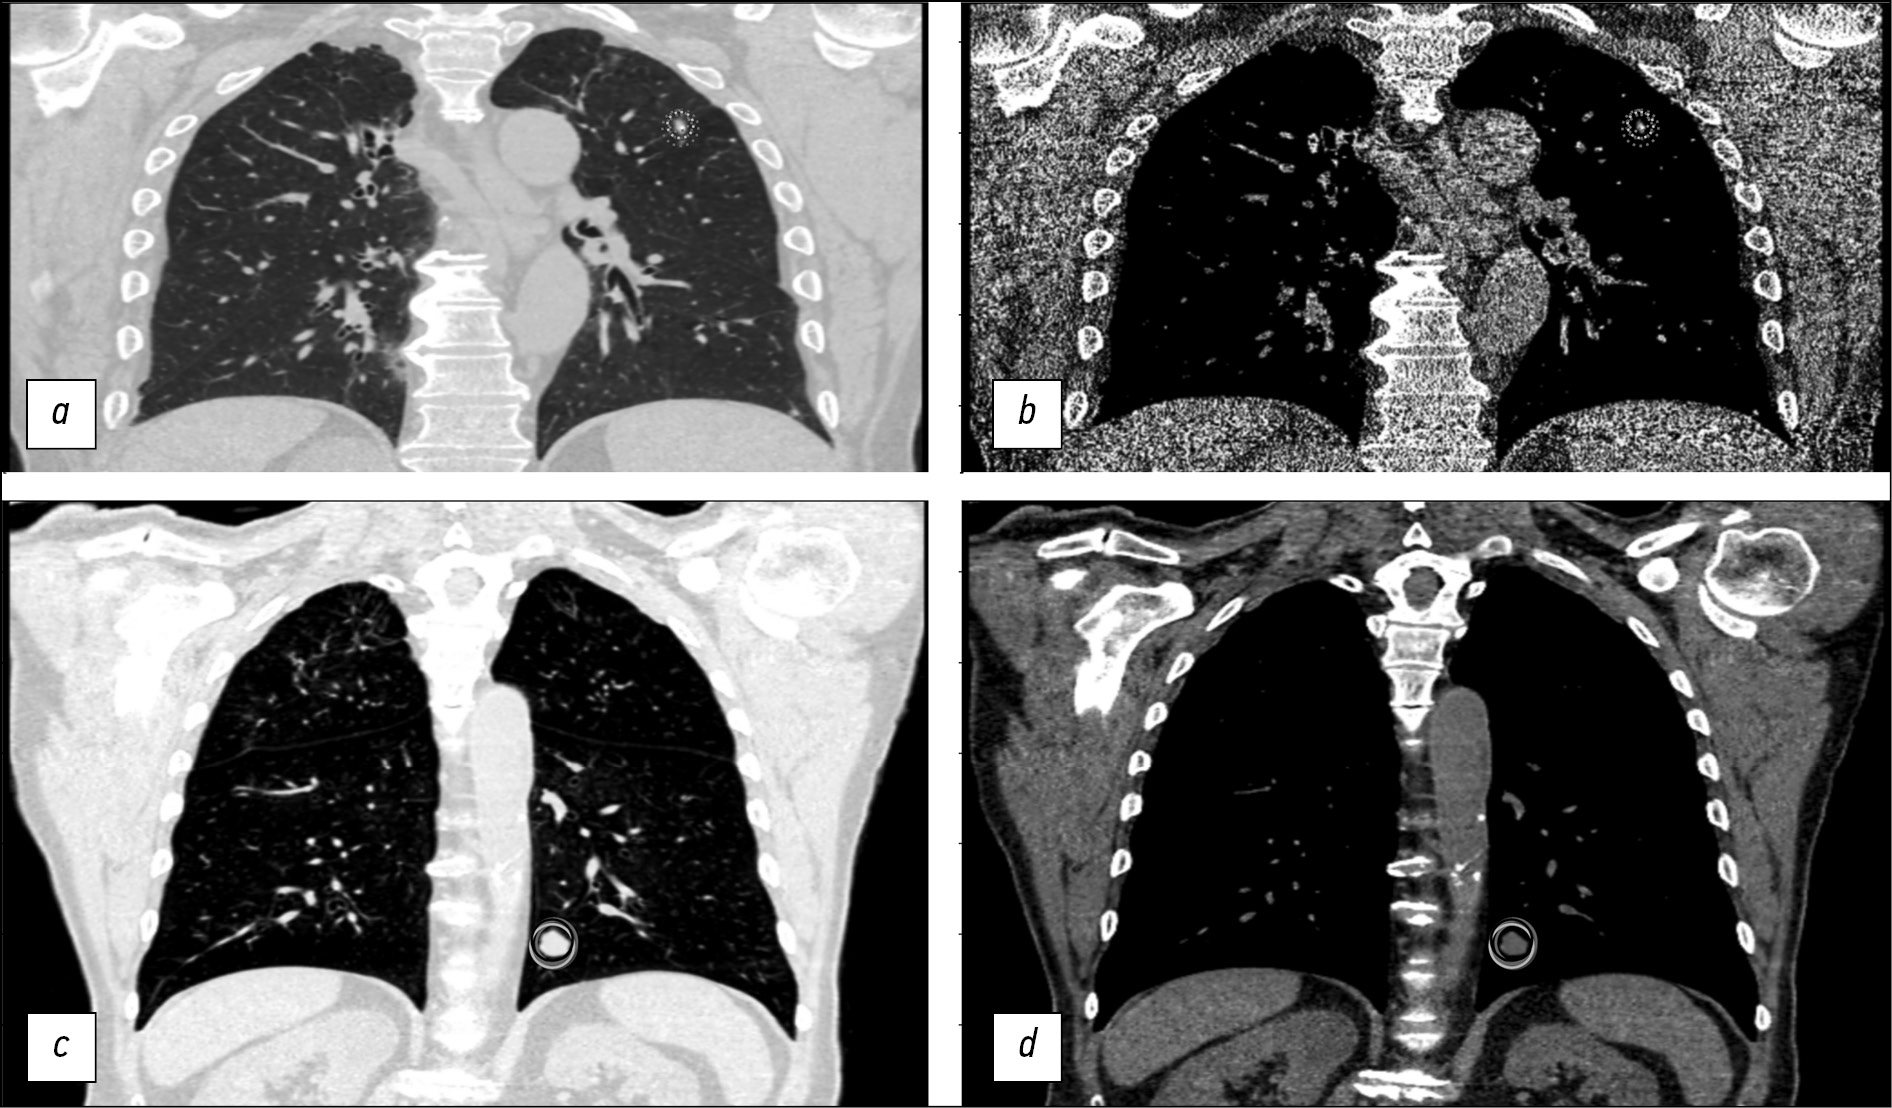

Fig. 2. Examples of CT studies with significant disagreement (a, b, CTLungCa-500 AN RLADD02000018919, ID RLSDD02000018855) and full agreement (c, d, CTLungCa-500 AN RLAD42D007-25151, ID RLSD42D007-25151) between experts. The studies are presented in frontal projection in pulmonary (a, c) and soft tissue (b, d) modes. The radiologists' marks are shown with different colors: a, b - the focus was marked by five primary experts out of six, four assigned it a solid type and one - a semi-solid one. The arbiter disagreed with their opinion, recognizing the find as benign calcification; c, d - All six primary assessors and the arbiter classified the lesion as potentially malignant solid.

In the present work, when classifying the assessments of primary experts to the categories of FN, TN, FP, and TP, we relied on the assumption that all pulmonary nodules will be tagged on each CT scan. However, the study results indicated that the study participants limited themselves to the five largest pulmonary lesions on CT scans, following the recommendations given to them. Thus, some pulmonary nodules were ignored by individual radiographers, which affected their diagnostic accuracy and the inter-agreement values in expert pairs. Nevertheless, differences in the opinions between primary experts are a desirable outcome when using arbitration because they expand the range of tagged lesions. This condition reduces the proportion of FN findings, even under artificial restrictions on the number of nodules to be tagged. One of the main outcomes of this work is that consensus among several radiographers is not a prerequisite for proper tagging of datasets. The arbitrators bear the main responsibility because they must correctly interpret all entities noted by the primary experts (Figs. 2a and 2b).